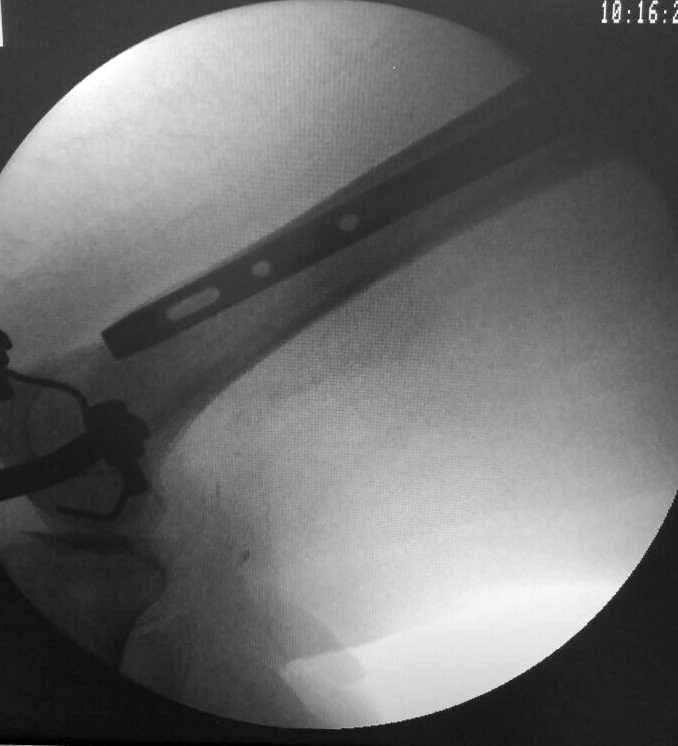

А есть картинка проксимального отдела в профиль? Не слишком ли задняя там точка входа?

Это длинная псевдограмма, как понимаете, Ее сложно сзади завести, с ЭОПа только эта картинка, я за соседним столиком оперировал, парни пытались погнуть - обломился, в итоге поставили короткую, репозиция примерно такая же, снимки могу завтра -послезавтра выложить. У нас уже были проблемы с этим стержнем в плане переднего Кортекса, да и другие тоже, у них на проксимальный винте не "борозды" , а "царапины" - либо блокировать наглухо либо ротационной стабильности нет, да и прямая как шпага((((

Как-то так

Точку входа сделать чуть спереди или чуть сзади - не вижу никакой сложности. С такой формой гвоздя - лучше чуть спереди.

А как гнули и где обломился? Если по отверстию - то еще куда ни шло, а если по телу гвоздя - тут да, повод встревожиться. А вообще - лучше их все взять, да аккуратно зажимая в тисках, загнуть дистальный конец гвоздя градусов на 5 кзади.